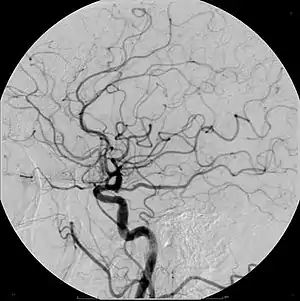

- Angiography (arterial investigations)

Iodinated contrast contains iodine. It is the main type of radiocontrast used for intravenous administration. Iodine has a particular advantage as a contrast agent for radiography because its innermost electron ("k-shell") binding energy is 33.2 keV, similar to the average energy of x-rays used in diagnostic radiography. When the incident x-ray energy is closer to the k-edge of the atom it encounters, photoelectric absorption is more likely to occur. Its uses include: